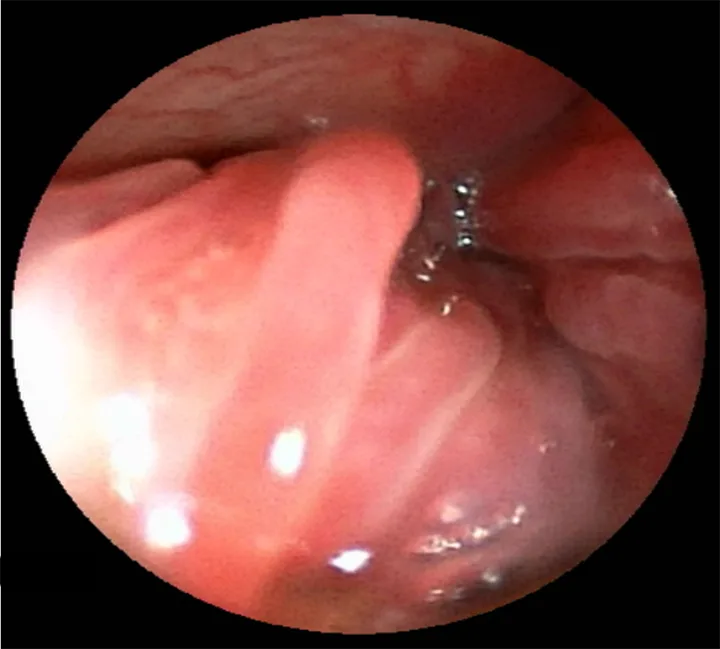

Rhinoscopy

A rigid or flexible rhinoscope can visualize nasal passages, and flexible rhinoscopy can achieve retroflexed views of the nasopharynx (Figure 3). Rhinoscope-guided biopsy may be possible, depending on the size and type of scope compared with the patient. Blind biopsy can be performed if guided biopsy is not possible and should ideally be based on CT and/or rhinoscopy images.

Rhinoscopy image of turbinates in a dog.

FIGURE 3

Rhinoscopy image of mildly erythematous turbinates in the left nasal cavity of an 11-year-old spayed Australian shepherd with lymphoplasmacytic rhinitis